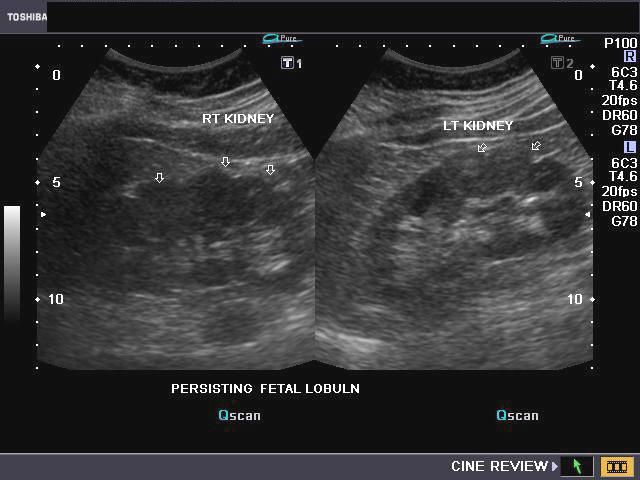

5-Fetal lobulations

في مرحلة تطور الجنين تتكون الكلية عن طريق تلاحم عدة فصوص lobes. وهذه الفصوص قد تستمر إلى مابعد مرحلة البلوغ. تظهر بشكل تموجات في القشرة الخارجية للكلية. من المهم أن لا نخطئ في تشخصيها كندبة scar أو ورم في الكلية.